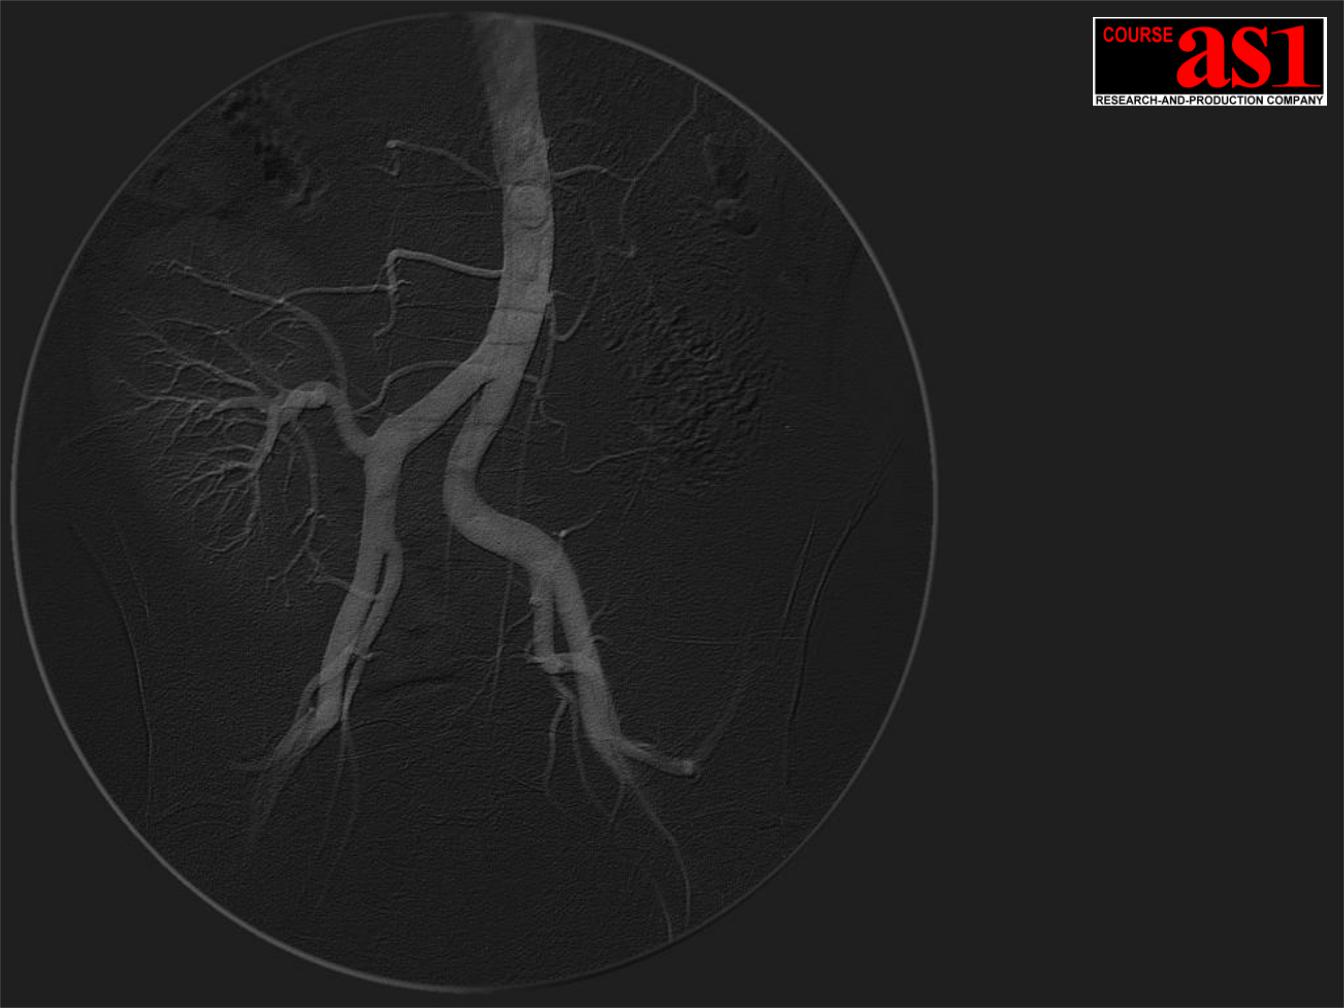

Слева X-Ray Система |

Реального Времени |

“AS_RTDR-1M30” |

( внизу - DSA обработка |

в формате QuickTime) |